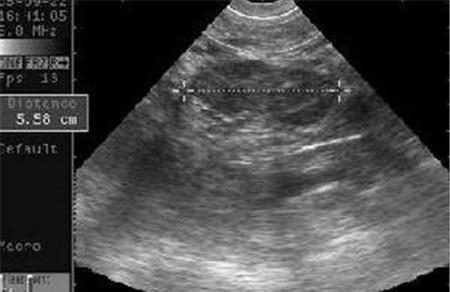

卵巢黄体破裂要住院吗 视情况而定 卵巢黄体破裂要不要住院主要还是看自己的情况,建议先去医院做个检查。卵巢黄体破裂在一次出血后可逐渐自行凝集而止血,出血量多少悬殊很大,从数10ml以至数百,上千毫升不等,具体情况要根绝您的出血量看是否要住院治疗以及住院治疗的时间。 卵巢黄体破裂要住院吗-卵巢黄体破裂如何诊断 1.患者无停经史,发病往往在两次月经期中间或月经前期,性交后发病。 2.腹部检查有明显压痛、反跳痛。内出血多者,叩诊有移动性浊音。 3.妇科检查,子宫正常大小,后穹窿触痛,附件可触及边界不清的包块,有压痛。 4.血常规检查:白细胞正常或稍高,红细胞及血红蛋白下降。 5.阴道后穹窿穿刺可抽出不凝血液。 6.必要时行妇科B超、腹腔镜检查。